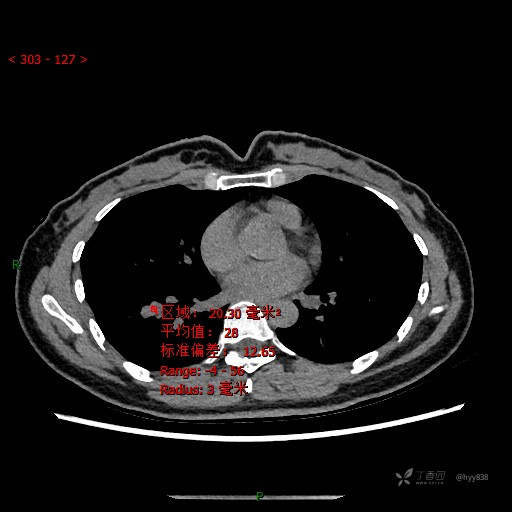

CT值